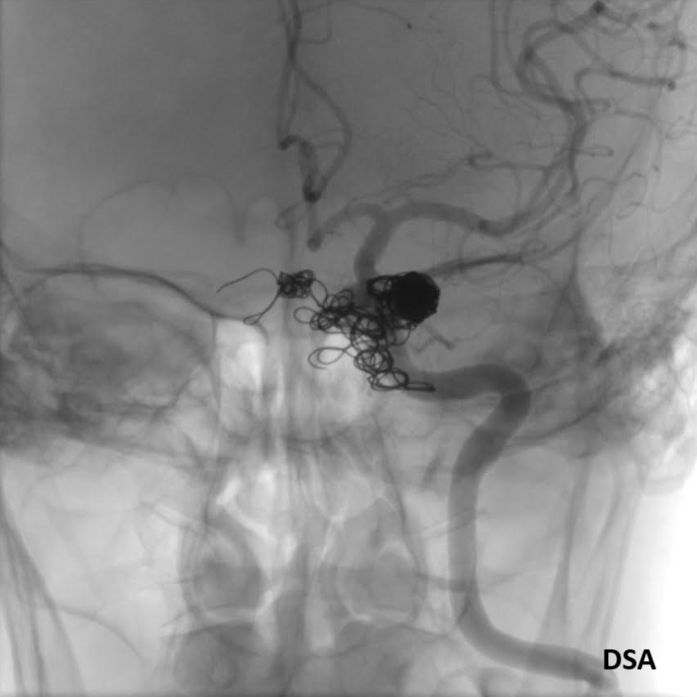

- C) DSA incelemelerinde sol eksternal karotid arter (ok) kateterizasyonunda kontrast maddenin kavernöz sinüse (ok) geçtiği izleniyor. Tedavi sonrası görüntüde kavernöz sinüs ile karotis arteriyel sistem arasında bulunan fistül traktına coil embolizasyon (ok) işlemi uygulandığı görülüyor.

- Karotikokavernöz fistül tanısı için; tonometri ve pnömotonometri gibi klinik testler ile radyolojik görüntüleme yöntemlerinden yararlanılmaktadır. Altın standart görüntüleme olarak da Dijital Substraksiyon Anjiyografi (DSA) kullanılmaktadır.

- DSA incelemelerine göre fistüller direkt ve indirekt olarak sınıflandırılmaktadır.

- DSA: Fistülün akış hızını karakterize ederek direkt ve indirekt fistülleri net olarak ayırabilir. ICA defektinin tam anatomik yerini ve ICA veya ECA dural besleyicilerini gösterir. Ayrıca DSA ile endovasküler tedaviler yapılabilmektedir.

- Olgumuzun DSA incelemelerinde sol ICA ve ECA’dan kavernöz sinüse fistülöz bağlantı olduğu izlenmiş ve coil embolizasyon işlemi uygulanarak tedavi edilmiştir.